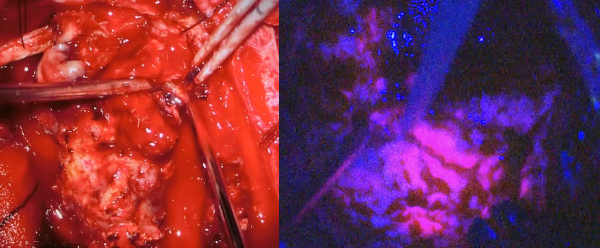

手術には光線力学的診断剤のアラベル(アミノレブリン酸塩酸;5-ALA)を併用します。5-ALAから生合成されるプロトポルフィリンIXが選択的に腫瘍細胞に蓄積し、これに励起光を照射すると赤色蛍光が発せられることから腫瘍が明瞭に見えます。これに電気生理学的モニタリングを併用し、手術操作による神経機能の温存を目標とし、細部にわたり腫瘍を取り除くよう努めております。